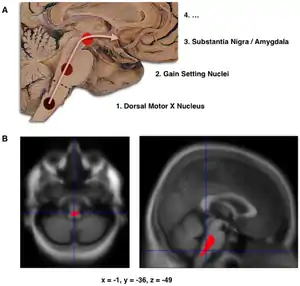

The main pathological characteristics of PD are cell death in the brain's basal ganglia (affecting up to 70% of the dopamine secreting neurons in the substantia nigra pars compacta by the end of life).[70] In Parkinson's disease, alpha-synuclein becomes misfolded and clump together with other alpha-synuclein. Cells are unable to remove these clumps and the alpha synuclein becomes cytotoxic, damaging the cells.[11][77] These clumps can be seen in neurons under a microscope and are called Lewy bodies. Loss of neurons is accompanied by the death of astrocytes (star-shaped glial cells) and a significant increase in the number of microglia (another type of glial cell) in the substantia nigra.[78] Braak staging is a way to explain the progression of the parts of the brain affected by Parkinson's disease. According to this staging, PD starts in the medulla and the olfactory bulb before moving to the substantia nigra pars compacta and the rest of the midbrain/basal forebrain. Movement symptom onset is associated when the disease begins to affect the substantia nigra pars compacta.[14]

- Schematic initial progression of Lewy body deposits in the first stages of Parkinson's disease, as proposed by Braak and colleagues

- Localization of the area of significant brain volume reduction in initial PD compared with a group of participants without the disease in a neuroimaging study, which concluded that brainstem damage may be the first identifiable stage of PD neuropathology[79]